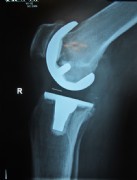

Example of a complete prosthesis

An older total endoprothesis inluding replacement of the kneecap. However, today, we replace kneecaps only very rarely.

Center left and center right: A modern knee prosthesis with sparing bone removal and sliding surface replacement. Such knee joints are used routinely by us. They are made for the particular patients affected knee.